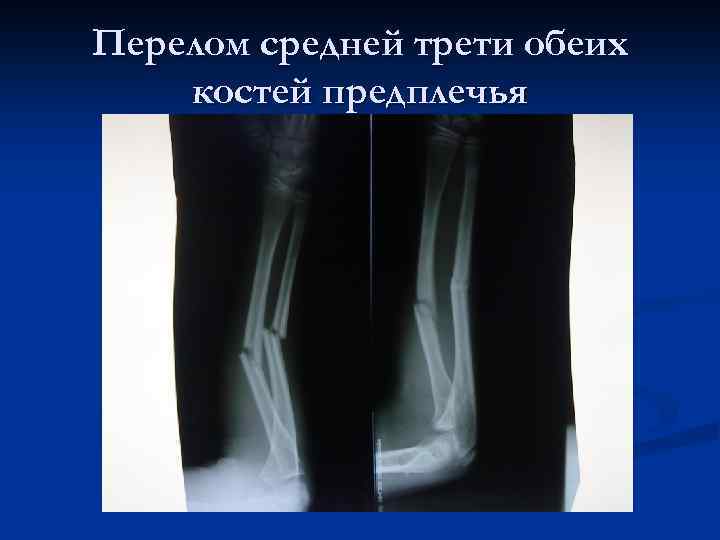

Перелом средней трети обеих костей предплечья